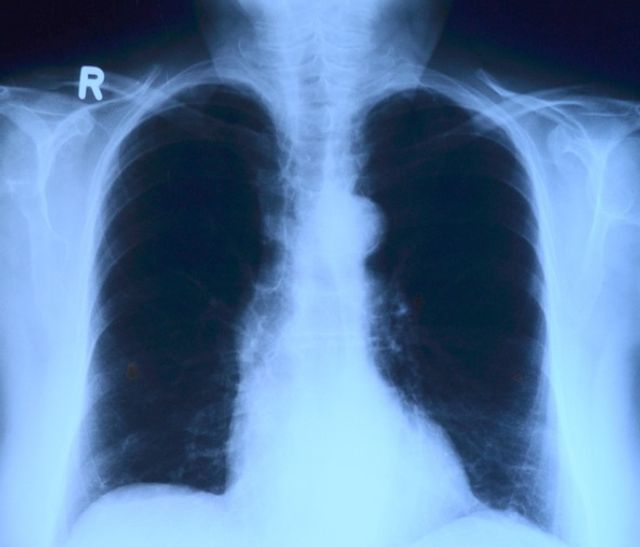

В комментарии ГУФСИН указано: «Схема лечения, назначенная осужденному пациенту, включала в себя антибактериальные препараты широкого спектра действия, которые применяются в том числе и для лечения бактериальной пневмонии. Противотуберкулезные препараты пациенту были необходимы, так как он был в контакте с больными туберкулезом. На фоне лечения рентгенологически от 22.03.2018 была положительная динамика».

Почему положительная динамика привела к смерти пациента от другой болезни и известно ли было врачам о пневмонии, в релизе не поясняется. У правозащитников, которые сейчас занимаются делом Иванова, комментарий ГУФСИН вызвал недоумение.